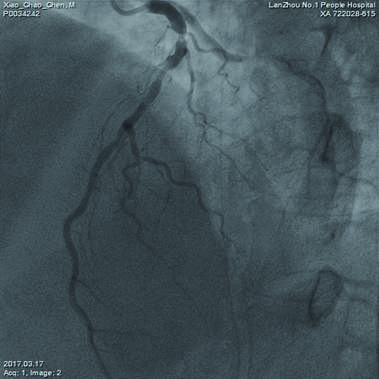

1 资料与方法患者,男性,62岁。曾因“反复胸闷、胸前区疼痛5月余”,就诊于当地医院。患者在住院期间病情加重,于2017年3月6日14:00以急性心肌梗死急诊转入甘肃省心血管病研究所。查体:血压88/45 mmHg,心率69次/min,双肺底部可听及中等量湿性啰音,心音低钝,心脏瓣膜听诊区未闻及病理性杂音,心电图异常,ST-T改变,提示前壁心肌梗死。抽血化验,立即送入导管室行紧急经皮冠状动脉介入治疗。冠脉造影提示:左前降支6段以后100%闭塞,前向TIMI血流0级,左回旋支100%阻塞,前向TIMI血流0级,右冠状动脉(RCA)2段60%狭窄,内膜不光整,前向TIMI血流2级(图 1)。

| 图 1 经皮冠状动脉介入治疗前左前降支与回旋支均完全堵塞,心肌梗死溶栓治疗血流0级 |